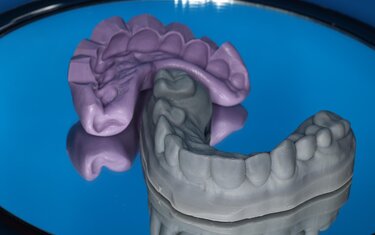

The teeth were prepped (Figure 9), scanned and new restorations designed in CAD software (Chairside CAD, Exocad). We then 3D printed a model and filled the putty wash matrix (Figure 10) with a self-cure composite material (Luxatemp Ultra, DMG) to create temporaries for the patient to wear for a week to get feedback on fit, function and color (Figure 11).

Figure 10: From the scan of the final design, a model was 3D printed

and a putty wash matrix used to create temporaries.